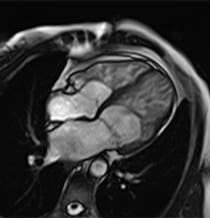

Image of normal heart.

Image of a normal heart.

What Is Left Ventricular Non-Compaction Cardiomyopathy (LVNC)?

In LVNC, muscle in the heart's left ventricle — one of two lower chambers — becomes sponge-like, with extra space between the muscle tissues. These heart muscle changes can affect how the left chamber pumps blood and can allow blood clots to form in the chamber.